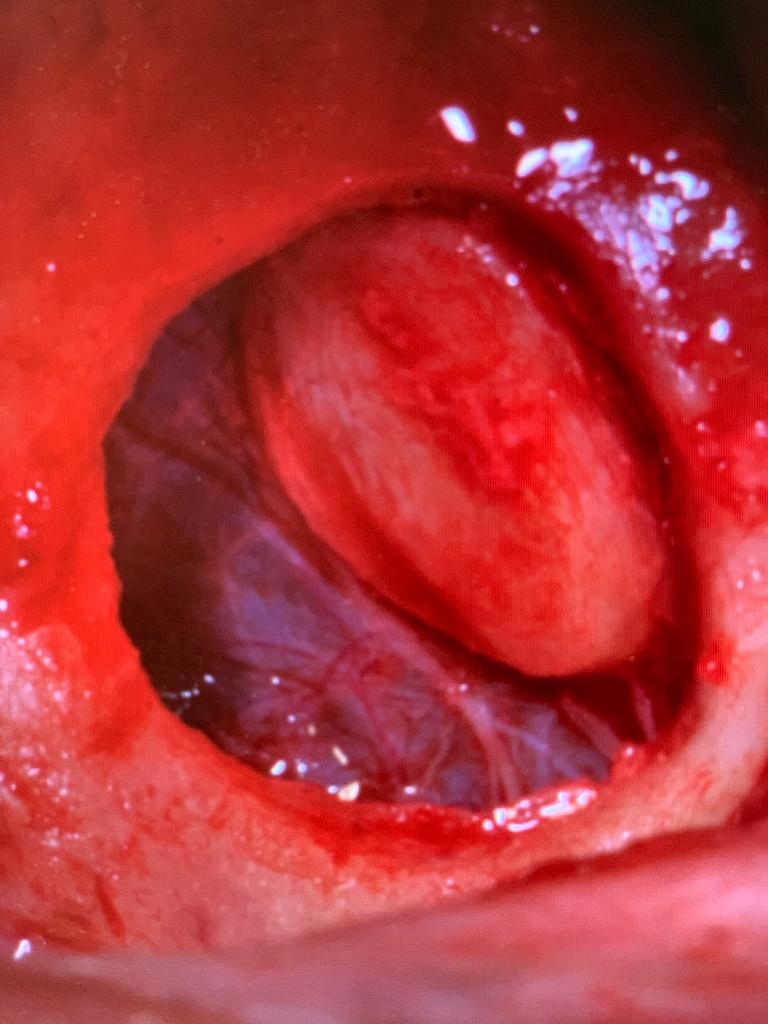

Sinus Lateral Approach